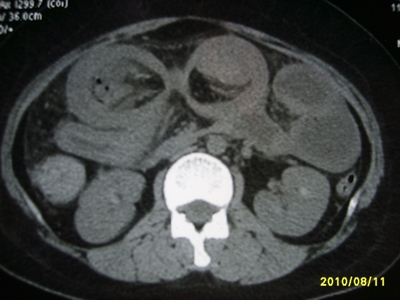

5天前突发腹痛剧烈难忍,伴解淡血水样便。近一天来腹痛缓解,没有明显的腹膜炎的体征。今天照的腹部ct。从ct上看感觉是一个绞窄性肠梗阻,但是现在没有腹痛。不好解释

要有麻烦了,感觉小肠有套叠还有扭转改变,估计部分已有坏死。

高位肠梗阻(不全性),原因小肠(空肠)扭转,肠壁水肿增厚,成年人肠梗阻要排除合并占位,建议手术。

绞窄性肠梗阻_肠管套叠 扭转,肠壁明显水肿。

病人现在没有腹痛。怪了。从影像上来看。确实是绞窄了。但是没有腹痛。没有明显的腹膜炎的体征。确实有不好解释。难道是坏死了。反而不痛了。怪怪怪

支持绞窄性肠梗阻,肠壁明显水肿并见有多发小泡状积气--肠坏死

考虑绞窄性肠梗阻并肠坏死。